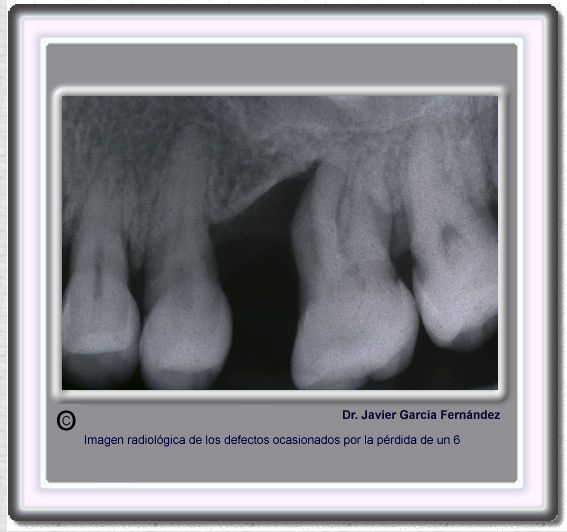

image440